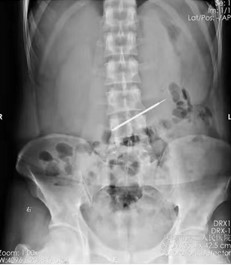

适用于金属或高密度异物,胸、腹部正侧位X线片可了解异物数量、大小、形态及位置,硬币类圆钝消化道异物需随访X线,以观察异物的位置,是否存在嵌顿的情况。

腹腔异物(硬币) 腹腔异物(铁丝)